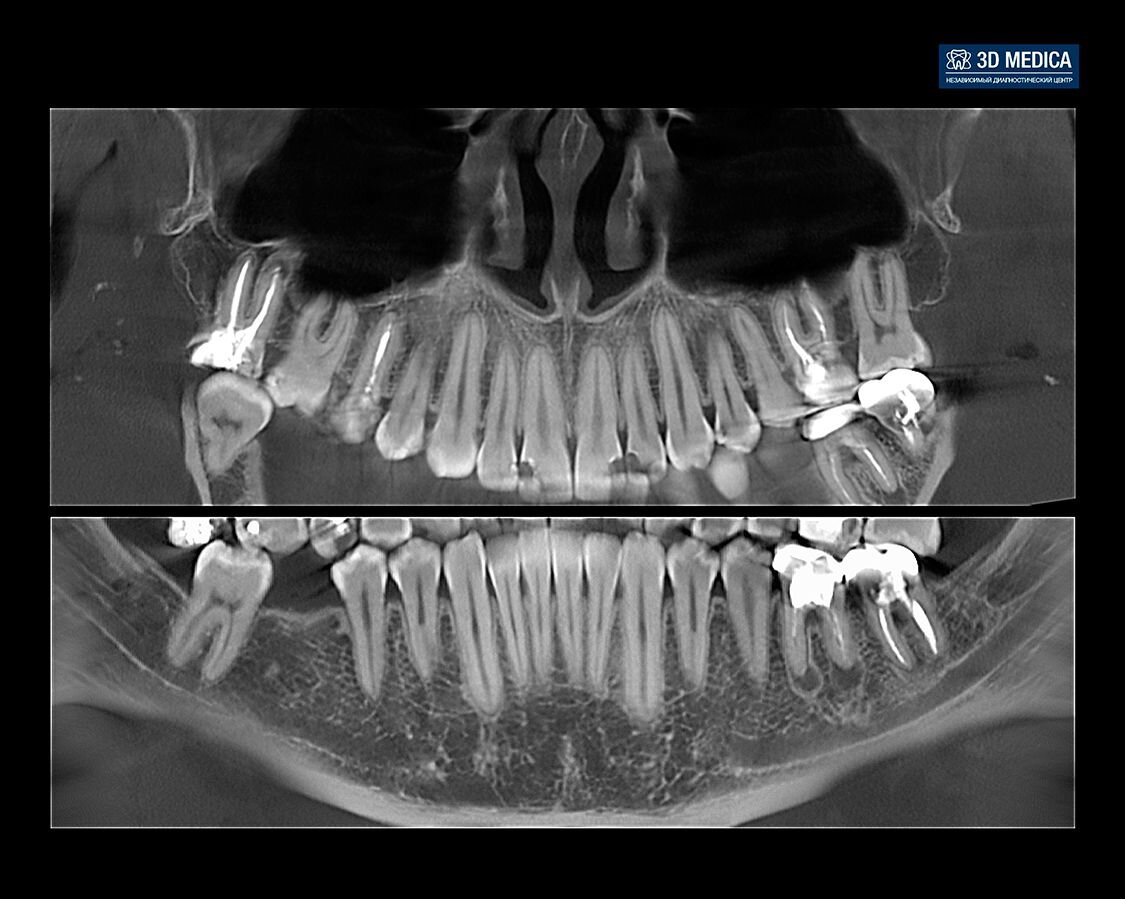

• Компьютерная томография. Без кт никуда, тк имеется очень много анатомических нюансов — уровень костной ткани и расположение верхнечелюстной пазухи, расположение нижнечелюстного нерва, также с помощью кт можно выявить наличие воспалений в области верхушек корней соседних зубов.